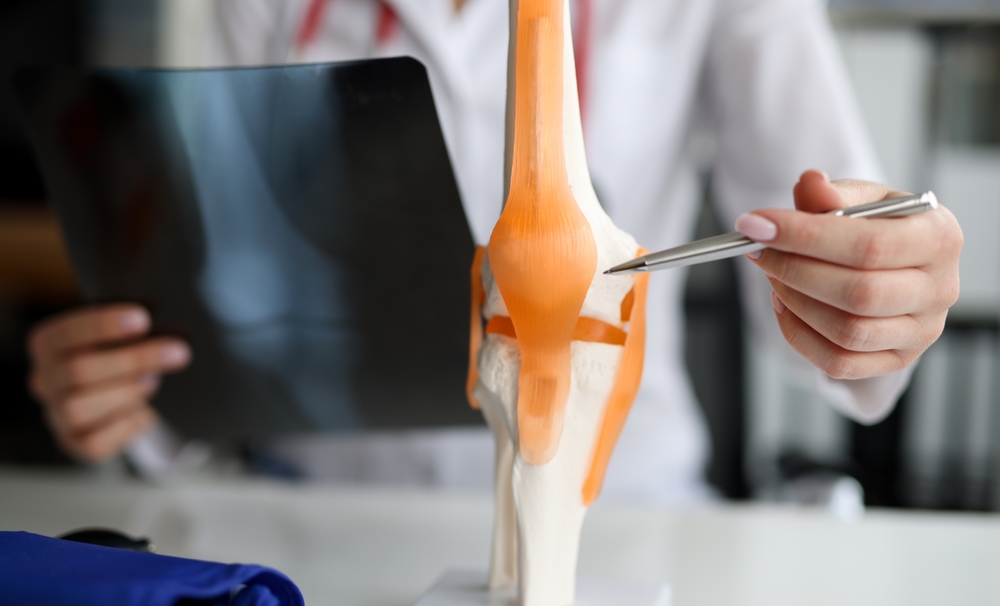

What Joints Can Be Replaced . Learn more about the different types of. Joint replacement surgery involves removing a damaged joint and replacing it with a new joint. Replacing a joint can relieve pain and help you move and. Other joints, such as the thumb, big toe, and finger joints can also be replaced when necessary. The doctor may suggest a joint replacement to improve how you live. Joint replacement surgeries can be of the hip, knee, shoulder, ankle, elbow and fingers. The knees, hips, ankles, shoulders, wrists, and elbows can all be replaced. The most common joints replaced are hip, knee, ankle, wrist, shoulder, and elbow. Surgeons can replace many joints, such as the: However, hip and knee replacements are considered the. The prosthesis is designed to replicate the movement of a normal, healthy joint. Total joint replacement is a surgical procedure in which parts of an arthritic or damaged joint are removed and replaced with a metal, plastic or ceramic device called a prosthesis.

Total joint replacement is a surgical procedure in which parts of an arthritic or damaged joint are removed and replaced with a metal, plastic or ceramic device called a prosthesis. However, hip and knee replacements are considered the. Joint replacement surgeries can be of the hip, knee, shoulder, ankle, elbow and fingers. Joint replacement surgery involves removing a damaged joint and replacing it with a new joint. The most common joints replaced are hip, knee, ankle, wrist, shoulder, and elbow. The prosthesis is designed to replicate the movement of a normal, healthy joint. Replacing a joint can relieve pain and help you move and. Surgeons can replace many joints, such as the: Learn more about the different types of. The knees, hips, ankles, shoulders, wrists, and elbows can all be replaced.

What Joints Can Be Replaced The prosthesis is designed to replicate the movement of a normal, healthy joint. Total joint replacement is a surgical procedure in which parts of an arthritic or damaged joint are removed and replaced with a metal, plastic or ceramic device called a prosthesis. Joint replacement surgeries can be of the hip, knee, shoulder, ankle, elbow and fingers. The most common joints replaced are hip, knee, ankle, wrist, shoulder, and elbow. Learn more about the different types of. Joint replacement surgery involves removing a damaged joint and replacing it with a new joint. The doctor may suggest a joint replacement to improve how you live. The prosthesis is designed to replicate the movement of a normal, healthy joint. However, hip and knee replacements are considered the. Replacing a joint can relieve pain and help you move and. Surgeons can replace many joints, such as the: Other joints, such as the thumb, big toe, and finger joints can also be replaced when necessary. The knees, hips, ankles, shoulders, wrists, and elbows can all be replaced.